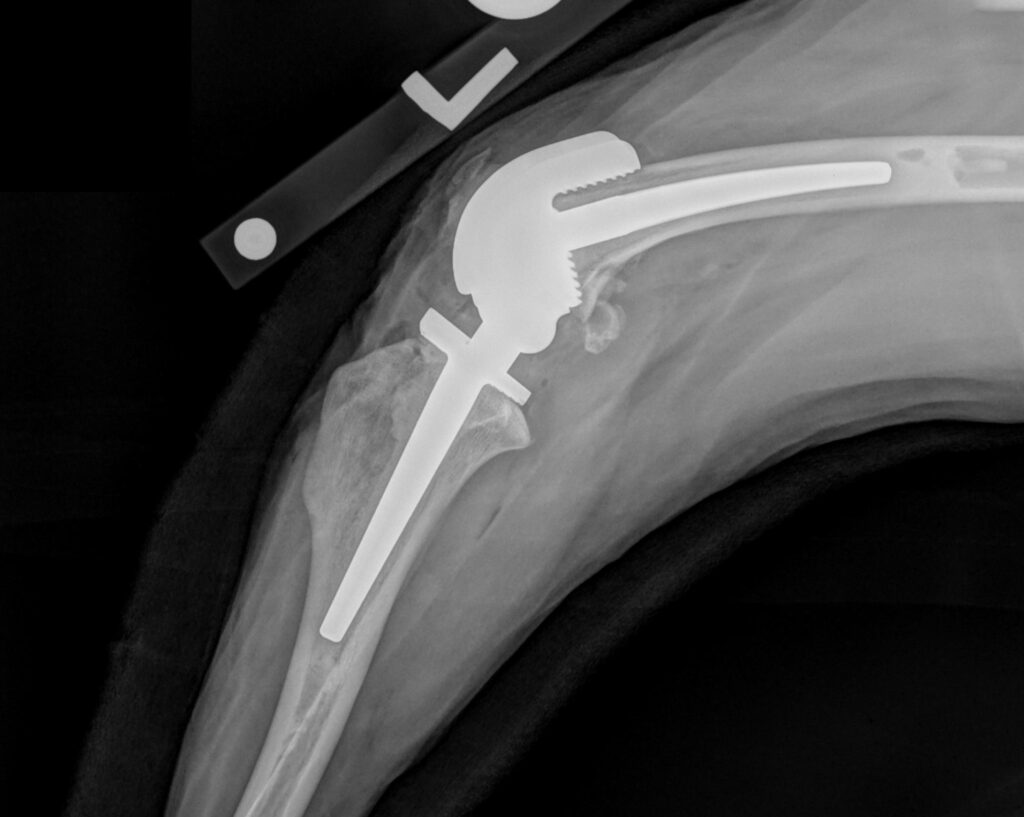

Limb sparing/salvage

Unique options to Fitzpatrick Referrals in limb sparing and salvage for treating trauma and cancer in the forelimb or hind limb.